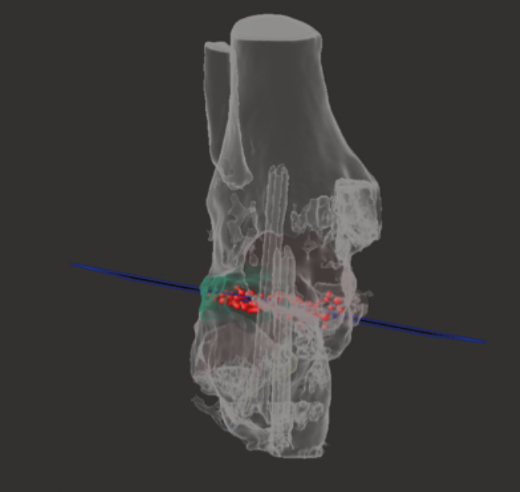

Caso 3. Pseudoartrosis subastragalina

Se trata de un caso del Dr. Cuervas-Mons, publicado en Techniques in Orthopedics(15), acerca de un paciente varón de 54 años que acude a la consulta con dolor del retropié y deformidad en varo. Tras la valoración, se evidencia pseudoartrosis sintomática (Figura 9), por lo que se decide llevar a cabo tratamiento quirúrgico.

Se presenta un problema: la identificación del plano de pseudoartrosis es fácil de manera preoperatoria con el uso de imágenes; sin embargo, la identificación del plano de pseudoartrosis completo de manera intraoperatoria puede ser difícil, siendo necesario una resección ósea amplia y en ocasiones insuficiente.

Utilidad de la impresión 3D: se decidió imprimir una guía 3D de corte como ayuda intraoperatoria. La guía permite la resección de la coalición de manera completa y reducir la necesidad de guía con fluoroscopia.

- Obtención de las imágenes (Figura 10).

- Identificación del plano de pseudoartrosis (Figura 11).

- Diseño de la guía de corte guiada por aguja de Kirschner (Figura 12).